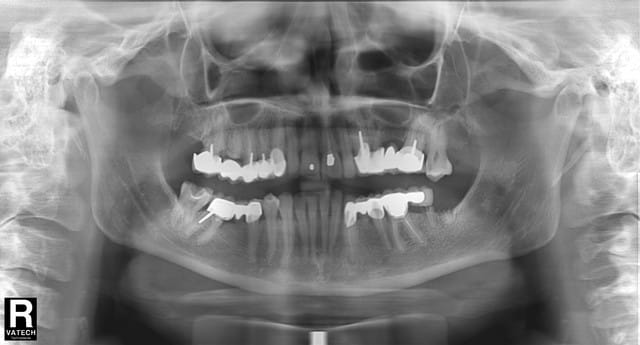

J'ai reçu récemment un jeune patient de 24 ans qui me pose un cas de conscience.

Il présente de nombreuses couronnes et bridges, pas franchement glorieux voire merdiques par endroit bien que très récents d'après ses dires. Il présente aussi des dents postérieures (genre 7 et 8, pas les 6) avec des reprises carieuses majeures sous des soins dégueulasses, des dents à l'état de racine à extraire, bref rien ne va.

Aujourd'hui je récupère un patient désespéré par l'état de sa bouche. Les racines dont les prothèses ont été perdues sont foutues, et le pire c'est que les autres trucs faits par le prédécesseur compliquent tout : en gros il faudrait défaire ce qui a été fait avant de recommencer à propre ! Il faudrait finalement mettre le prix d'une voiture dans la bouche de ce patient, et il ne le peux absolument pas.

Le patient est pret à faire un crédit pour remettre tout ça en ordre, mais je ne peux m'empêcher de penser que ça serait au praticien indélicat de mettre la main à la poche pour rattraper son boulot médiocre... J'attends de voir le bilan long cône que je lui ai prescrit pour m'en assurer, mais avec ce que j'en vois déjà je m'attends à trouver des endos merdiques sous les prothèses en place.

Je fais mes retraitements moi-même. Quant au status si là je veux qu'il soit nickel c'est parce que dans ce cas précis il est possible qu'il soit utilisé comme "preuve" ou au moins comme outil de comparaison si le patient obtient sa pano d'avant les soins, donc je préfère que ça soit irréprochable.

On parle quand même d'un mec de 24 ans qui y a perdu sa 13 ainsi que 4 dents mandibulaires, sans parler de ce que je risque de découvrir en plus, c'est pas juste un composite raté sur la 38...